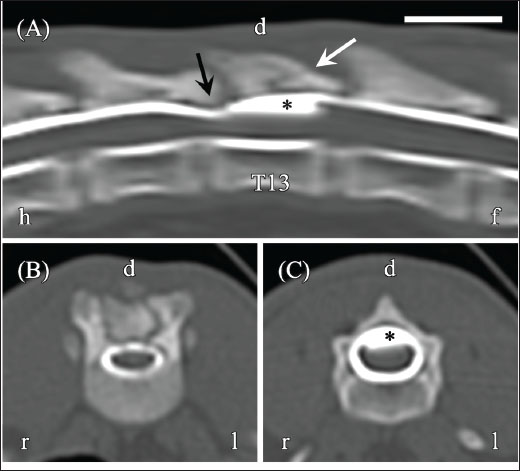

An approximately 7-month-old female Japanese domestic shorthair was referred to Matsuno Pet Clinic with paresis of both pelvic limbs and a history of back trauma since adoption. The cat had previously been treated with antibiotics for trauma, but pelvic limb paresis persisted. Approximately 1 month later (day −118), CT myelography was performed at Akita Komatsu Animal Hospital using a Brivo CT 385 scanner (GE Healthcare, Chicago, IL, USA) (slice thickness, 1.25 mm; reconstruction kernel, BONEPLUS). Iohexol (Omnipaque 240, 240 mg I/ml; GE Healthcare) was administered via lumbar puncture at a dose of 0.5 ml/kg under the guidance of C-arm fluoroscopy (Brivo OEC 785; GE Healthcare). Scans were obtained approximately 5 minutes after the injection. Contrast distribution and the presence or absence of extradural/intradural filling defects were assessed. A bone tissue window (window width, 3000 HU; window level, 500 HU) was used for analysis. These studies revealed spinal cord compression caused by a T13 vertebra fracture and a “teardrop sign” in the contrast column at the same site (Fig. 1A–C). Although no obvious fracture line was observed in T12, spinal cord compression due to dorsal lamina thickening was noted.

Fig. 1. Computed tomography (CT) myelography of the thoracolumbar vertebrae obtained 4 months prior (day−118). (A) Reconstructed sagittal CT myelography shows dorsal compression of the spinal cord (black arrow), a T13 vertebral fracture (white arrow), and teardrop-shaped fluid accumulation (asterisk) at the dorsal aspect of T13. (B) Transverse image at the T12–T13 level demonstrates spinal cord flattening. (C) Transverse image at the T13 level shows fluid accumulation (asterisk) compressing the dorsal spinal cord. Images were acquired using a bone tissue window (window width, 3,000 HU; window level, 500 HU). Orientation markers: h=head, f=foot, r=right, l=left. Scale bar=1 cm.